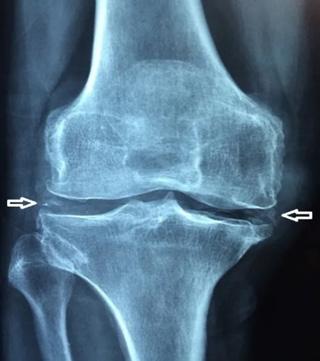

Existen evidencias radiológicas de OA que se correlacionan con la evolución del daño en 4 grados radiológicos:

♦ Grado 1: Esclerosis subcondral

♦ Grado 2: Estrechamiento articular

♦ Grado 3: Excresencias óseas (Osteofitos, geodas)

♦ Grado 4: Anquilosis

GRADO 1

Esclerosis subcondral

GRADO 2 Disminución del espacio articular

GRADO 3

Osteofitos y Geodas

GRADO 4

Malformación Anquilosis